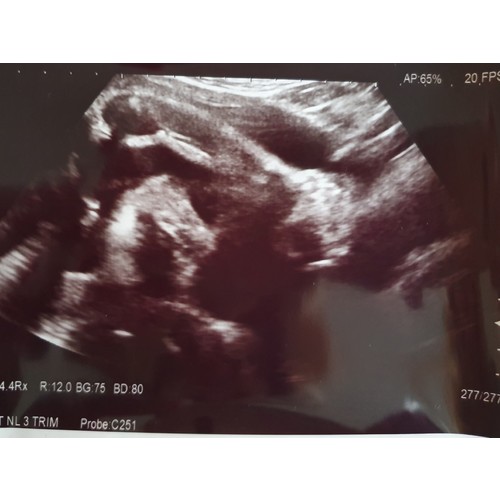

Ons meisje had geen zin in 3d foto’s van haar gezichtje en liet liever zien hoe lenig ze is 🤪